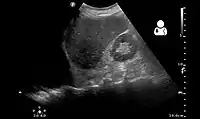

Ultrasonography may be used to detect hemothorax and other pleural effusions. This technique is of particular use in the critical care and trauma settings as it provides rapid, reliable results at the bedside.[23] Ultrasound is more sensitive than chest x-ray in detecting hemothorax.[25] Ultrasound can cause issues in people who are morbidly obese or have subcutaneous emphysema. When CT is unavailable in the current setting or the person cannot be moved to the scan, ultrasound is used.[3]

Ultrasound can detect blood in the pleural cavity. Blood in the thorax is shown by a uniform area without flocculation.[40] Pleural effusions without blood are usually hypoechoic. Echogenicity is indicated by cellular debris and/or fibrin. Bloody pleural effusions are shows by a swirling, hyperechoic pattern.[38] When a stethoscope is used (auscultation), the heartbeat sounds are faint. When percussion is performed, it produces a dull area. However, especially in traumatic cases, percussion may be painful. Although nonspecific, physical examinations may show reduced lung sounds and muffled, widespread heart sounds. Similar signs and symptoms may occur when other fluids are in the pleural cavity.[40]